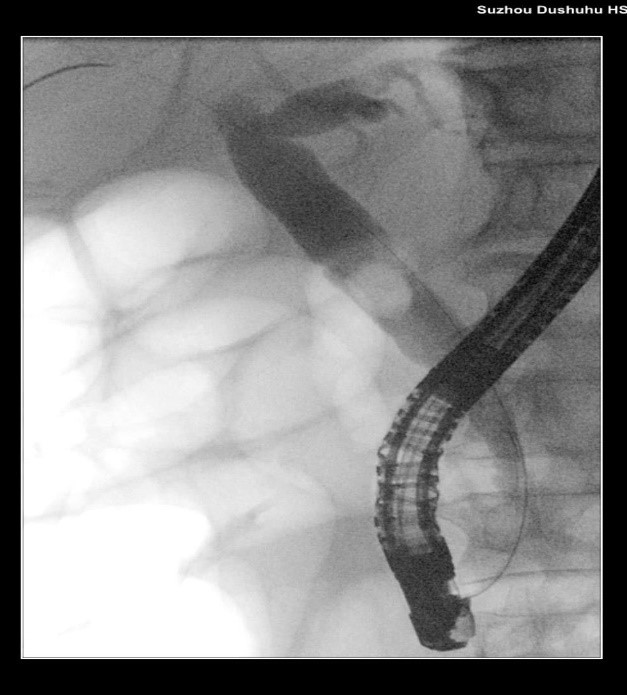

ERCP是通过将内镜经口插入十二指肠降部,经十二指肠乳头导入专用器械进入胆管或者胰管内,在X射线透视下注射造影剂造影、导入子内镜/超声探头观察,来完成对胆、胰疾病的诊断,并可以通过子内镜进行取石、扩张、放置支架等治疗操作。具有创伤小、恢复快、适用人群广的特点,但同时;但作为一种侵入性操作,也存在一定的风险和并发症,主要包括急性胰腺炎、胆管炎/脓毒血症、出血和肠穿孔等,少见并发症包括低血压、低血氧、空气栓塞等。不过,随着技术的不断进步和医生经验的积累,并发症的发生率已经逐渐降低。

苏大附四院ERCP团队在手术中看到陈大爷的胆总管在结石的影响下已经宽达13mm,结石大小11*10mm,将十二指肠乳头切开并扩张后用取石球囊把结石取出,置入胆管支架使胆汁充分引流,顺利解除了胆道梗阻。